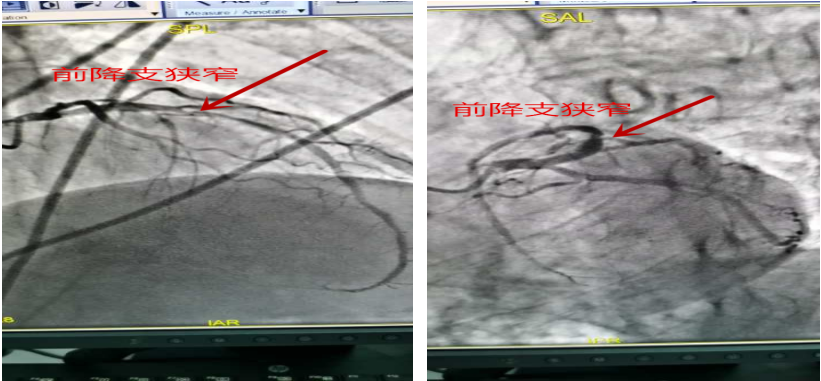

术前造影:患者右冠状动脉中段以远急性闭塞。

术前造影:患者前降支近段长病变,最重狭窄约85%。